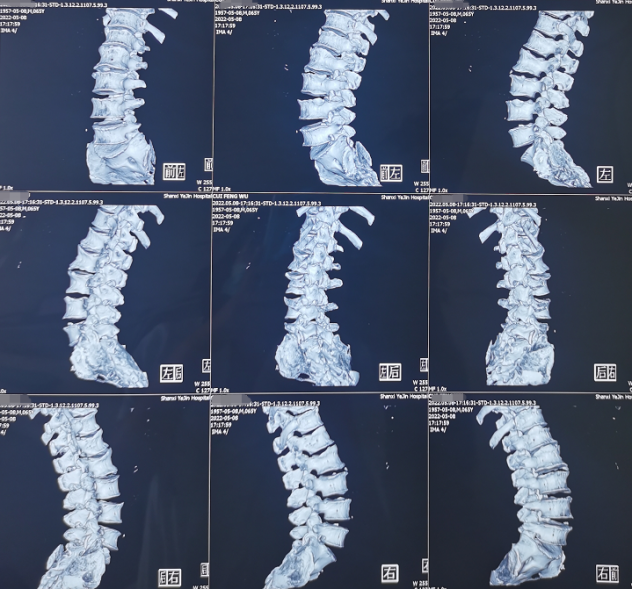

熊东主任接诊后,建议患者进行腰椎CT、核磁共振等影像检查和各项查体,结合各项检查结果,最终确诊患者为“腰椎间盘突出症(腰5/骶1,中央型)”。除此之外,患者还有相应水平的硬膜囊受压与腰椎骨质增生。

术前影像学资料: